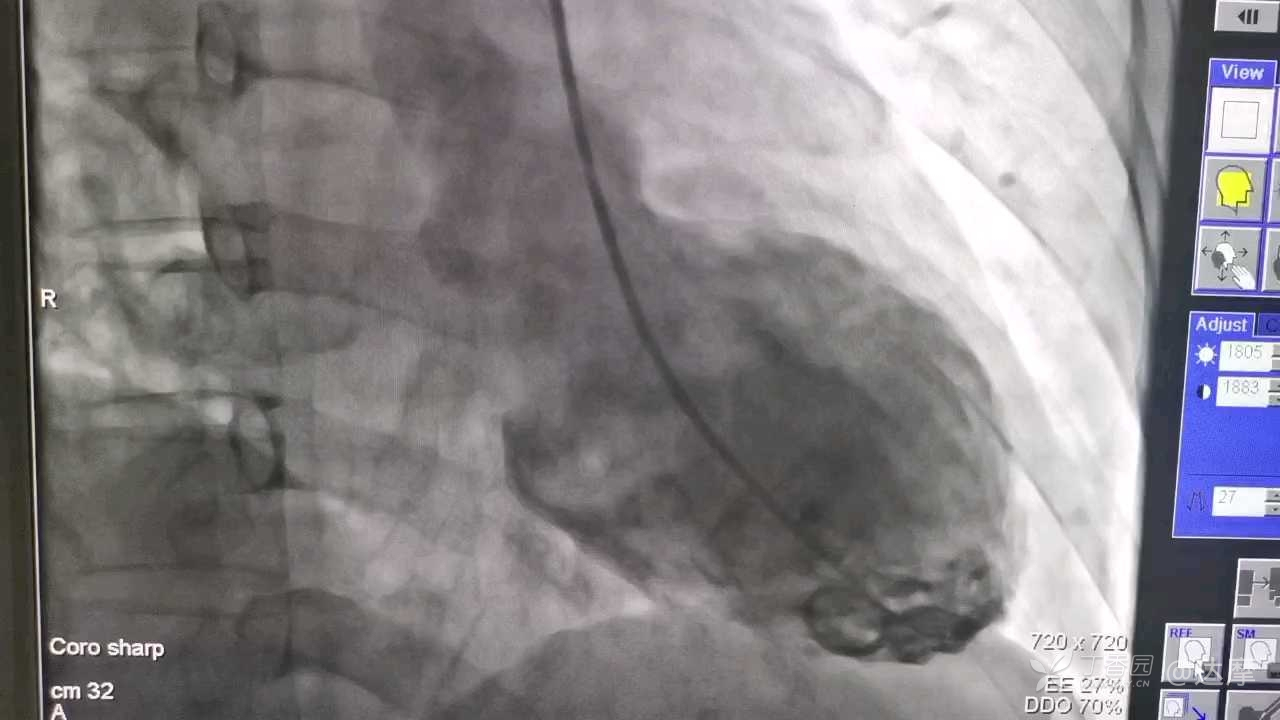

马上行了急诊冠脉造影和心室造影:

怎么样?有没有比这还典型的?有的话请大家分享一下。